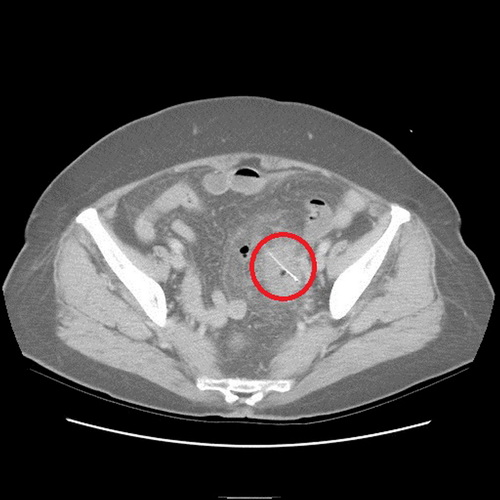

沒想到過了2天,老奶奶又來看診,醫師便為她安排住院檢查,經計算機斷層檢查,發現老奶奶乙狀結腸部份竟然有根2.5公分的魚刺,且魚刺已經穿破腸道,導致橫膈膜下方有氣體出現,經外科醫師協助開刀,終于順利幫老奶奶解決腹部不適的問題。